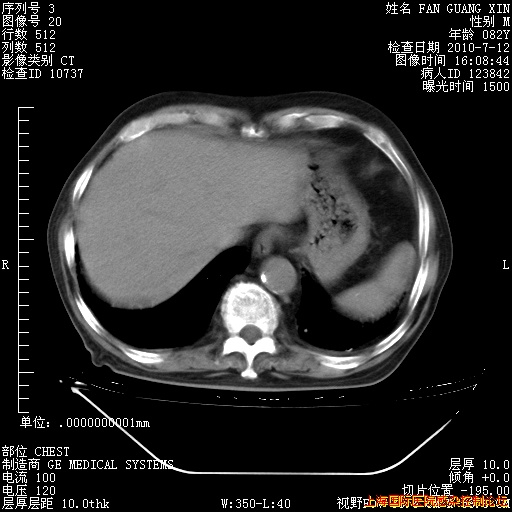

今天CT

整整相隔30天的肺部CT好像有所好转啊。甲强龙减量第3天,需要观察体温。